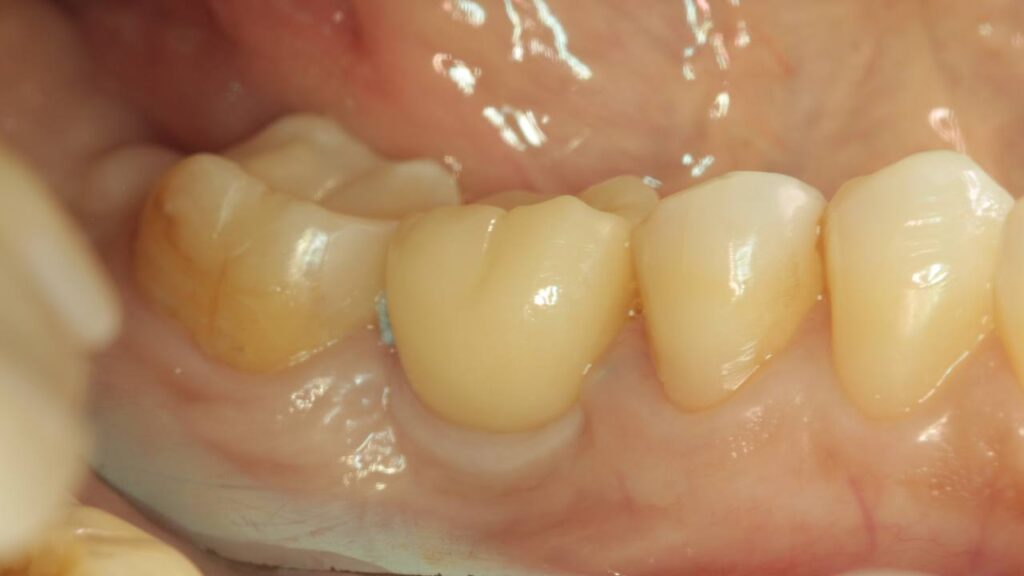

Протезирование коронками из диоксида циркония, после эндодонтического лечения — Исламов Л.А.(01.04.2026)